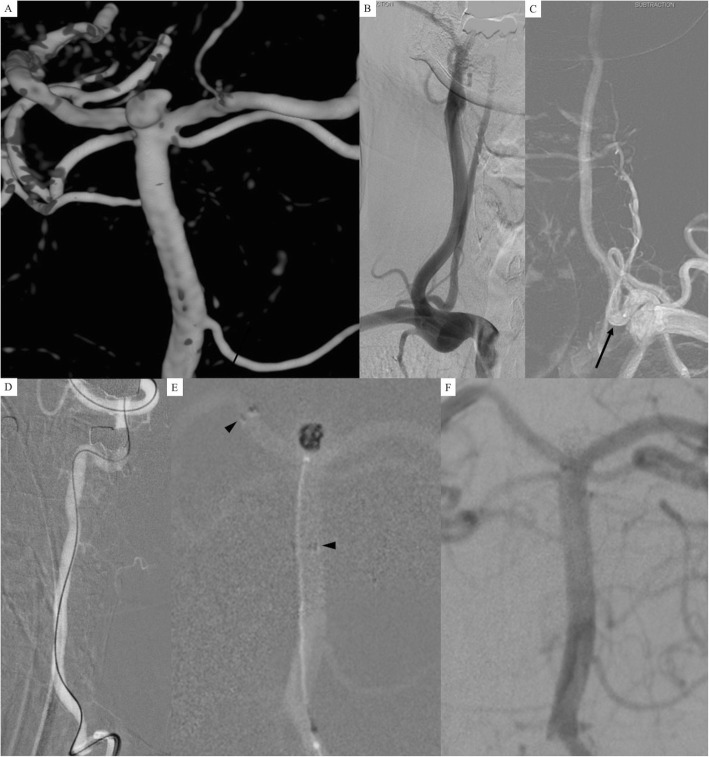

A 55-year-old woman presented with a long-standing history of headache. Her computed tomography (CT) and CT angiography revealed no intracranial hemorrhage and a basilar bifurcation aneurysm. DSA demonstrated a wide-necked (4.1 mm) basilar bifurcation aneurysm sized 4.9 mm with a daughter sac on left lateral side of the sac (Fig. 2a). On DSA, left proximal VA was dominant compared to right VA (Fig. 2b and c) so that we decided to select left VA for a guiding catheter during endovascular treatment. However, a 6-Fr guiding catheter could not pass through a left VA tortuosity at the proximal segment (a white arrowhead in Fig. 2d). Unfortunately, there was asymptomatic dissection of the left VA (a white arrow in Fig. 2d). We changed our plan for using a 5Fr-guiding catheter in the left VA and selected the right VA, which has a smaller diameter compared to the left VA. A single microcatheter (Excelsior SL-10 straight) was navigated to the right posterior cerebral artery and we deployed a Neuroform Atlas stent (4.0 mm × 21 mm) from the right posterior cerebral artery to the basilar artery (black arrowheads in Fig. 2e). After deploying the stent, the microcatheter was placed just proximal to the deployed stent (a black arrow in Fig. 2e). After removing the stent pusher wire, a 0.014-microwire and the same microcatheter were navigated easily through the stent to the aneurysm (Fig. 2f). Coiling was performed (Fig. 2g) and initial angiographic results showed a neck remnant of the aneurysm (Fig. 2h). On the 6-month follow-up angiography, the aneurysm was completely occluded (Fig. 2i).

Fig. 2.

a 3D-DSA demonstrated a wide-necked (4.1 mm) basilar bifurcation aneurysm sized 4.9 mm with a daughter sac on the left lateral side of the sac. b and c Left proximal vertebral artery (VA) was dominant compared to the right VA so that we decided to select the left VA for a guiding catheter during endovascular treatment. d A 6-Fr guiding catheter could not pass through the tortuosity of the left VA at the proximal segment (a white arrowhead). There was asymptomatic dissection of the left VA (a white arrow). e With a 5Fr-guinding catheter in the right VA, a single microcatheter (Excelsior SL-10 straight) was navigated to the right posterior cerebral artery and we deployed a Neuroform Atlas stent (3.0 mm × 21 mm) from the right posterior cerebral artery to the basilar artery (black arrowheads). After deploying the stent, the microcatheter was placed just proximal to the stent deployed (a black arrow). f A 0.014-microwire and the same microcatheter were navigated easily through the stent to the aneurysm. g Coiling was performed. h The initial angiographic result showed a neck remnant of the aneurysm. (i) On 6-month follow-up angiography, the aneurysm was completely occluded